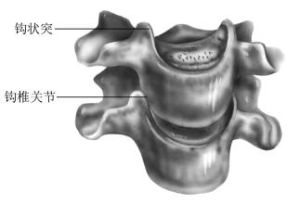

luschka關節該關節又稱Luschka關節,由第3~7頸椎的椎體鉤與上位椎體的唇緣所組成。

鉤椎關節的重要毗鄰:後方為脊髓、脊膜支和椎體的血管;後外側部構成椎間孔的前壁,鄰接頸神經根;外側有椎動靜脈和交感神經叢。隨年齡增長,椎體鉤常出現骨質增生, 可能壓迫脊神經或椎血管。

鉤椎關節是否一個真正的滑膜關節尚存在不同的看法,但近年來的觀察多數學者認為不是恆定的典型滑膜關節,5歲以後隨著頸段脊柱的運動而逐漸形成,是由直接連結向間接連結分化的結果。鉤椎關節的重要毗鄰:後方為脊髓、脊膜支和椎體的血管;後外側部構成椎間孔的前壁,鄰接頸神經根;外側有椎動靜脈和交感神經叢。隨年齡增長,椎體鉤常出現骨質增生,可能壓迫脊神經或椎血管。